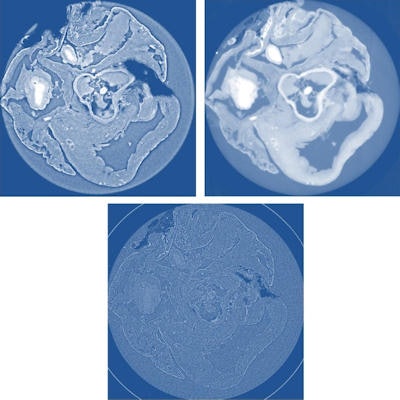

Top left: X-ray phase tomography slice of a rat's heart using propagation-based XPCi. Top right: X-ray phase tomography slice of a rat's heart using grating-based XPCi; the image has high contrast, but with some blurring compared to propagation-based XPCi. Bottom: conventional absorption-based x-ray CT with significantly lower contrast than phase-contrast scans.For SDPR, the simplest of XPCi techniques, acquisition at a single distance and approximations of the sample and wavefront properties are used to estimate the sample's phase shift. The technique works well as long as the imaged object has only small variations in composition, as typically found in soft tissue.

Using a tumor excised from a mouse model and a healthy rat heart, the researchers implemented the three techniques using the ID19 beamline at the ESRF with monochromatic 17.6 keV and 19 keV x-ray beams, respectively. A CCD detector with effective pixel sizes of 3-8 mm was used. In each scan, the samples were rotated through 360° and approximately 1,500 projections were acquired (Journal of Applied Physics, 21 October, 2014, Vol. 116:15, pp. 154903)

Examining image quality, significantly higher contrast-to-noise ratios (CNR) were observed for XGI scans, corresponding to more precise measurements of material density. For instance, in soft tissue in the heart, XGI gave a CNR of 55 compared with a range of 9-25 for the propagation-based techniques. For the same tissue, CNR values obtained from absorption scans constructed with the same data were less than one.

In a contrasting finding, HT and SDPR produced images with significantly better spatial resolution. Resolution for the two ranged from 8 mm to 12 mm, compared with 25 mm for XGI. The three techniques also varied in complexity. For example, data processing for SDPR, as well as acquisition, is the simplest of the three. Consequently, the researchers concluded that all three techniques are complementary tools that should be chosen according to the application.